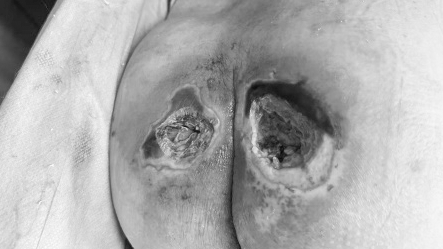

两个月逆袭

腐肉脱落 新肌重生

在团队的精准治疗和家属的细心护理下,王大爷的创面一天天好转:

• 换药1周后,感染得到控制,渗脓明显减少;

• 1个月后,

腐烂组织逐渐脱落,新鲜肉芽开始冒出;

• 两个月后,创面完全愈合,肉芽组织红润饱满,王大爷终于能安心翻身、坐起,不再受剧痛折磨。